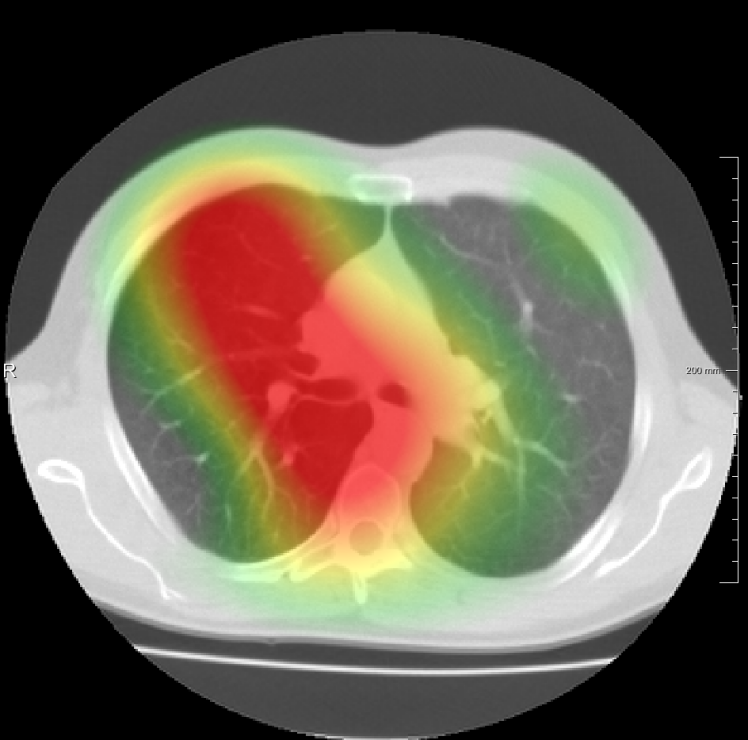

In total we generate 14 basis types of artificial DVFs: 5 single frequency, 4 mixed frequency, 4 respiratory motion and 1 identity. The precise settings of the parameters are available in Table I and examples are given in Fig. 4. The histograms of the Jacobians are also available in this figure. When the spatial frequency is increased, the Jacobian histograms will spread more, which shows that local relative volume changes are increased. The value of , the maximum artificial displacement along each axis, is chosen as 20, 15 and 7 for RegNet4, RegNet2 and RegNet1, respectively.

For the DIR-Lab-4DCT database, a comparison between RegNet and affine, B-spline (three resolutions), an advanced conventional registration method using sliding motion (Berendsen et al., 2014) and three other CNN-based methods (Eppenhof and Pluim, 2018; de Vos et al., 2019; Sentker et al., 2018) is available in Table IV. It can be seen that training with “S+M” improved performance slightly with respect to just “S”. Adding the respiratory motion category improved performance substantially, as these are inhale-exhale pairs; this is predominantly caused by the patients where the TRE after affine registration was still quite large. An example visualization is also available in Fig. 5(f), showing that adding the respiratory motion category can align images better in the diaphragm region. The advanced conventional registration method that leverages sliding motion (Berendsen et al., 2014) is still better than RegNet. Note that RegNet was not trained on the DIR-Lab-4DCT data, similar to Eppenhof and Pluim (2018); Sentker et al. (2018). However, de Vos et al. (2019) and Eppenhof and Pluim (2018)-DIR methods were trained on the same database but using cross-validation to report the results. Also note that the results reported in Sentker et al. (2018) are averaged over all phases of DIR-Lab-4DCT (T00 to T10), while the results of other CNN methods (including RegNet) are reported between the maximum inhale and maximum exhale phase (T00 and T50). These reported results are therefore likely somewhat better than the results for T00 and T50 only.